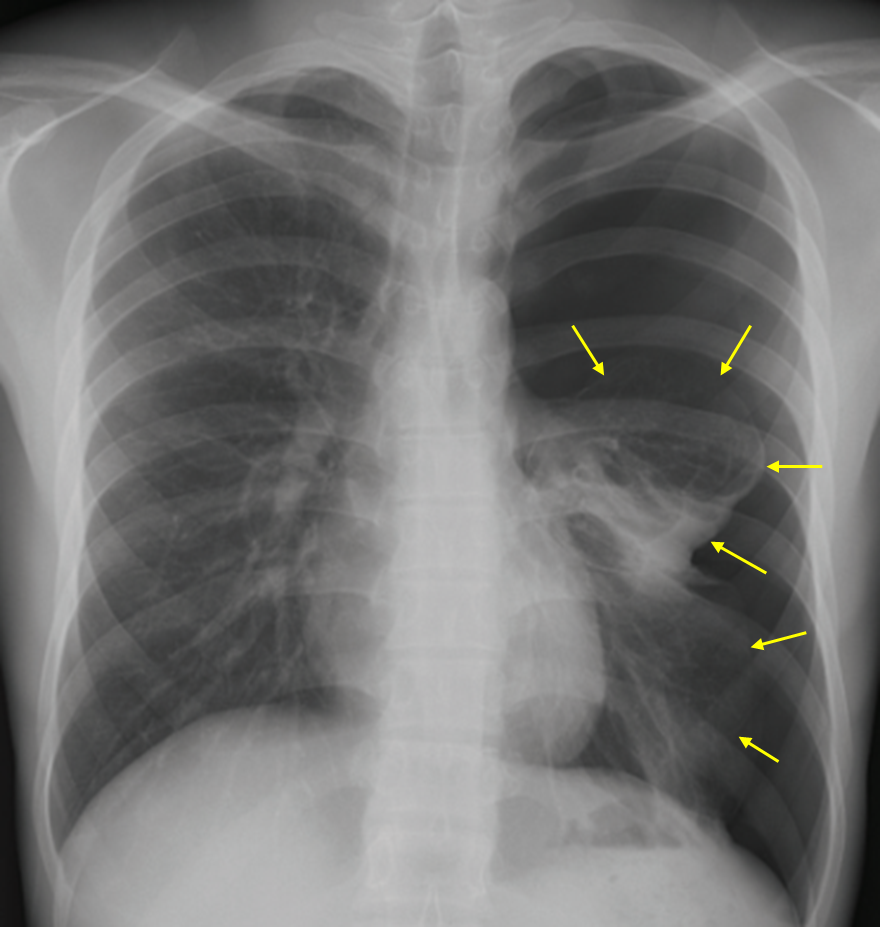

65세 남자가 3시간 전부터 왼쪽 가슴이 아프고 숨이 찬다며 병원에 왔다. 40갑 ∙ 년의 흡연자로 5년 전부터 만성폐쇄폐질환을 치료 중이다. 가슴 통증은 기침을 하거나 숨을 들이마실 때 더 심하다고 한다. 혈압 122/76 mmHg, 맥박 100회/분, 호흡 24회/분, 체온 36.6°C이다. 가슴 청진에서 왼쪽 가슴의 호흡음이 희미하게 들린다. 가슴 X선사진과 가슴 컴퓨터단층 촬영 사진이다. 치료는?

Img | CXR: 좌측 폐 pleural line CT: 좌측 기흉 |

• CXR과 CT에서 lung collapse, distal vascular marking의 소실이 확인되므로 기흉으로 진단한다.